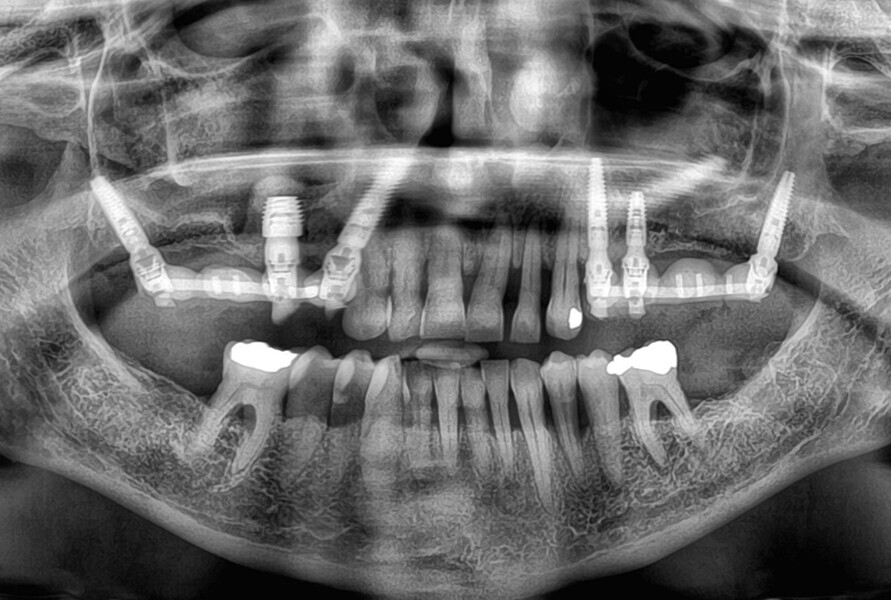

After a healing period of six months (Fig. 6), an intra-oral scan was performed at abutment level together with a scan of the existing temporary bridges in relation to the opposing arch (Figs. 7–11).